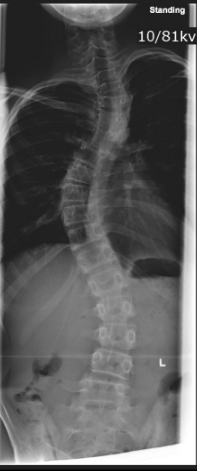

What is scoliosis?

Lateral spinal deviation >20°, often with rotation causing rib prominence.

How can you distinguish structural from non-structural scoliosis on side-bending?

Structural scoliosis does not correct with side bending; non-structural scoliosis to a reasonable extent corrects.

What assessment quantifies curve magnitude?

Cobb method.